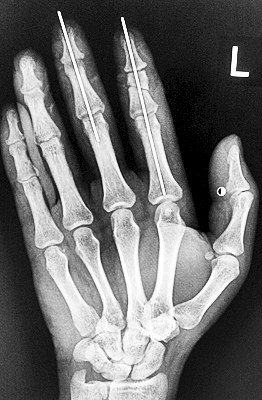

術(shù)后X光顯示,骨骼對位良好。

盧微波說,按照常規(guī),斷指再植只用接活3根血管和2根神經(jīng)就算成功。但為了讓該男子術(shù)后手指功能更好,盧微波和手術(shù)團(tuán)隊解剖出斷指的5根血管和4根神經(jīng)。

最終,盧微波和團(tuán)隊找好了需要的血管和神經(jīng),做好標(biāo)記后,開始固定食指骨骼、吻合肌腱,最后在顯微鏡下用直徑20微米的無創(chuàng)顯微縫合線開始吻合血管和神經(jīng)。

在經(jīng)過兩個多小時手術(shù)后,早上8時許,盧微波下令松止血帶,數(shù)十秒后男子蒼白的食指逐漸紅潤起來,食指在離體10個小時后恢復(fù)血運。

緊接著,盧微波又開始中指再植手術(shù)。上午10時許,中指在離體12小時后也成功恢復(fù)血運。